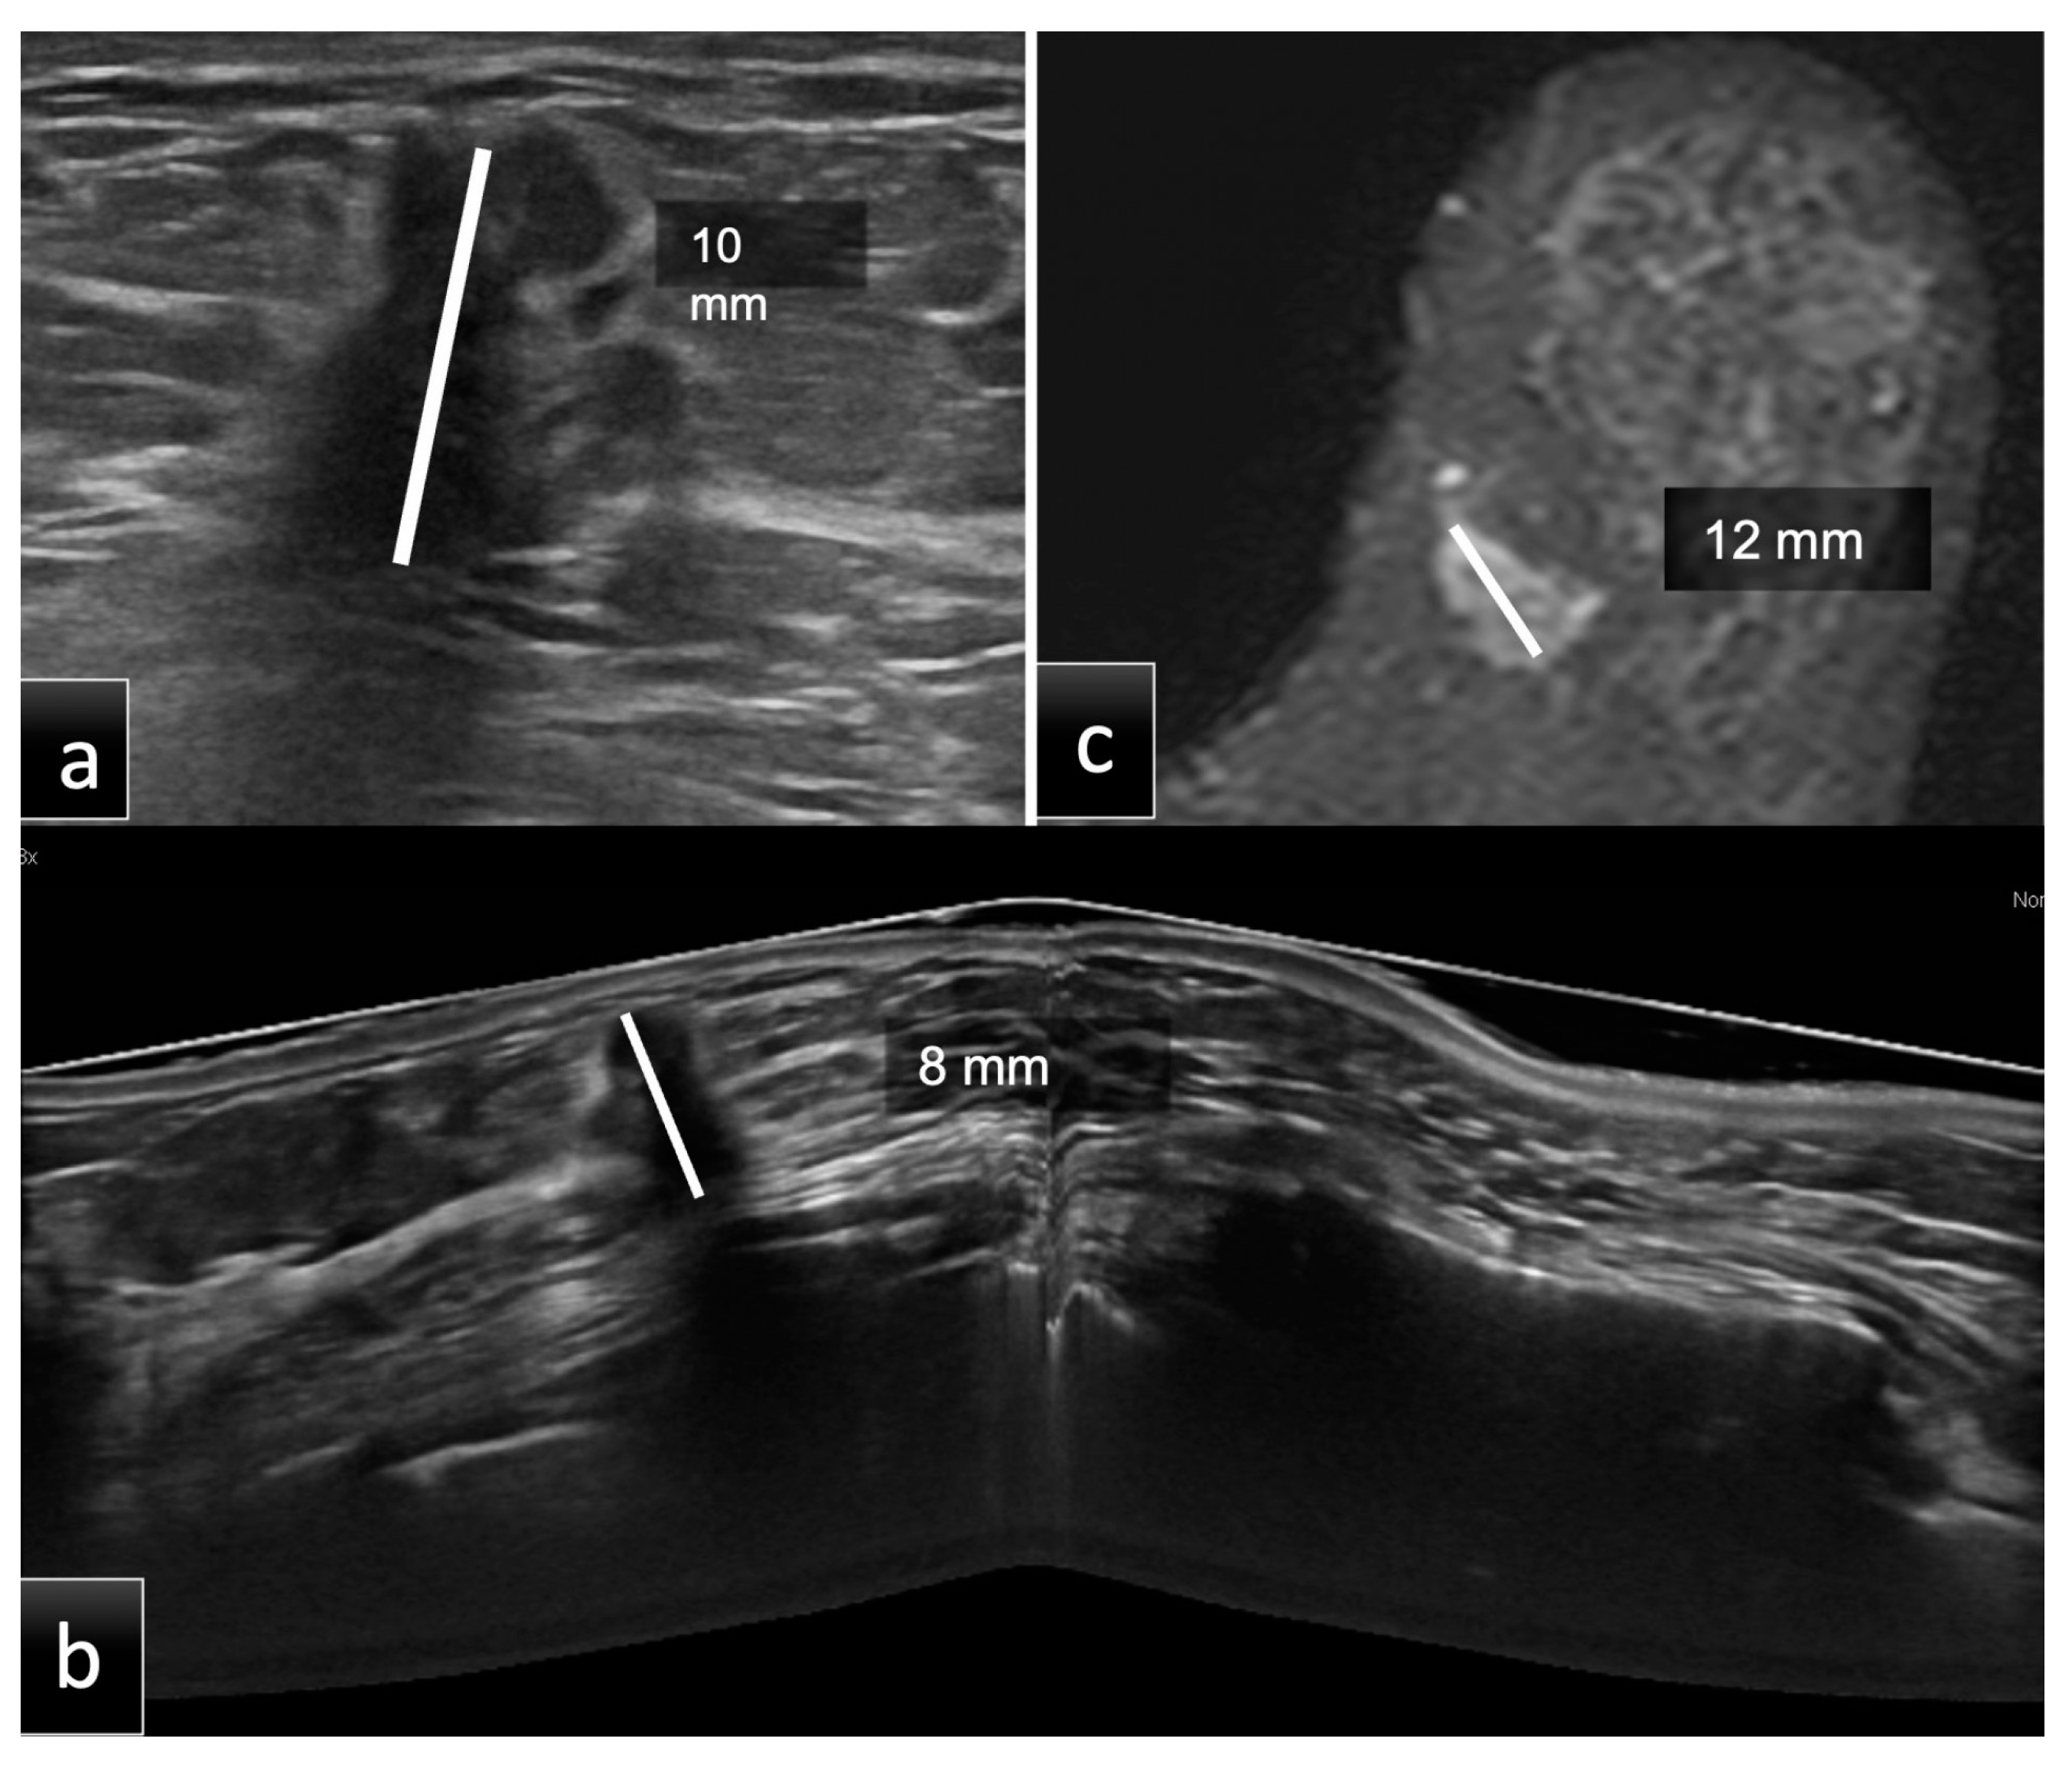

Figure 2.

Group 2, a 60-year-old patient with histological diagnosis of invasive ductal carcinoma (IDC) in the lower inner quadrant of the left breast. The maximum diameter measured on HHUS was 10 mm (a). At the same time, on CE-MRI, (c) the lesion had a maximum diameter of 12 mm. Prone 3D ABUS in the axial plane (b) showed a hypoechoic mass with irregular margins and the largest diameter of 8 mm. The histopathological size was 10 mm. ABUS and HHUS examinations were performed in both groups during the same study session by two different dedicated breast radiologists.